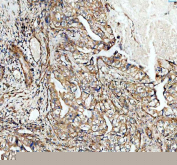

IHC staining of FFPE human rectum adenocarcinoma tissue with ADAM10 antibody, HRP-secondary and DAB substrate. HIER: boil tissue sections in pH8 EDTA for 20 min and allow to cool before testing.